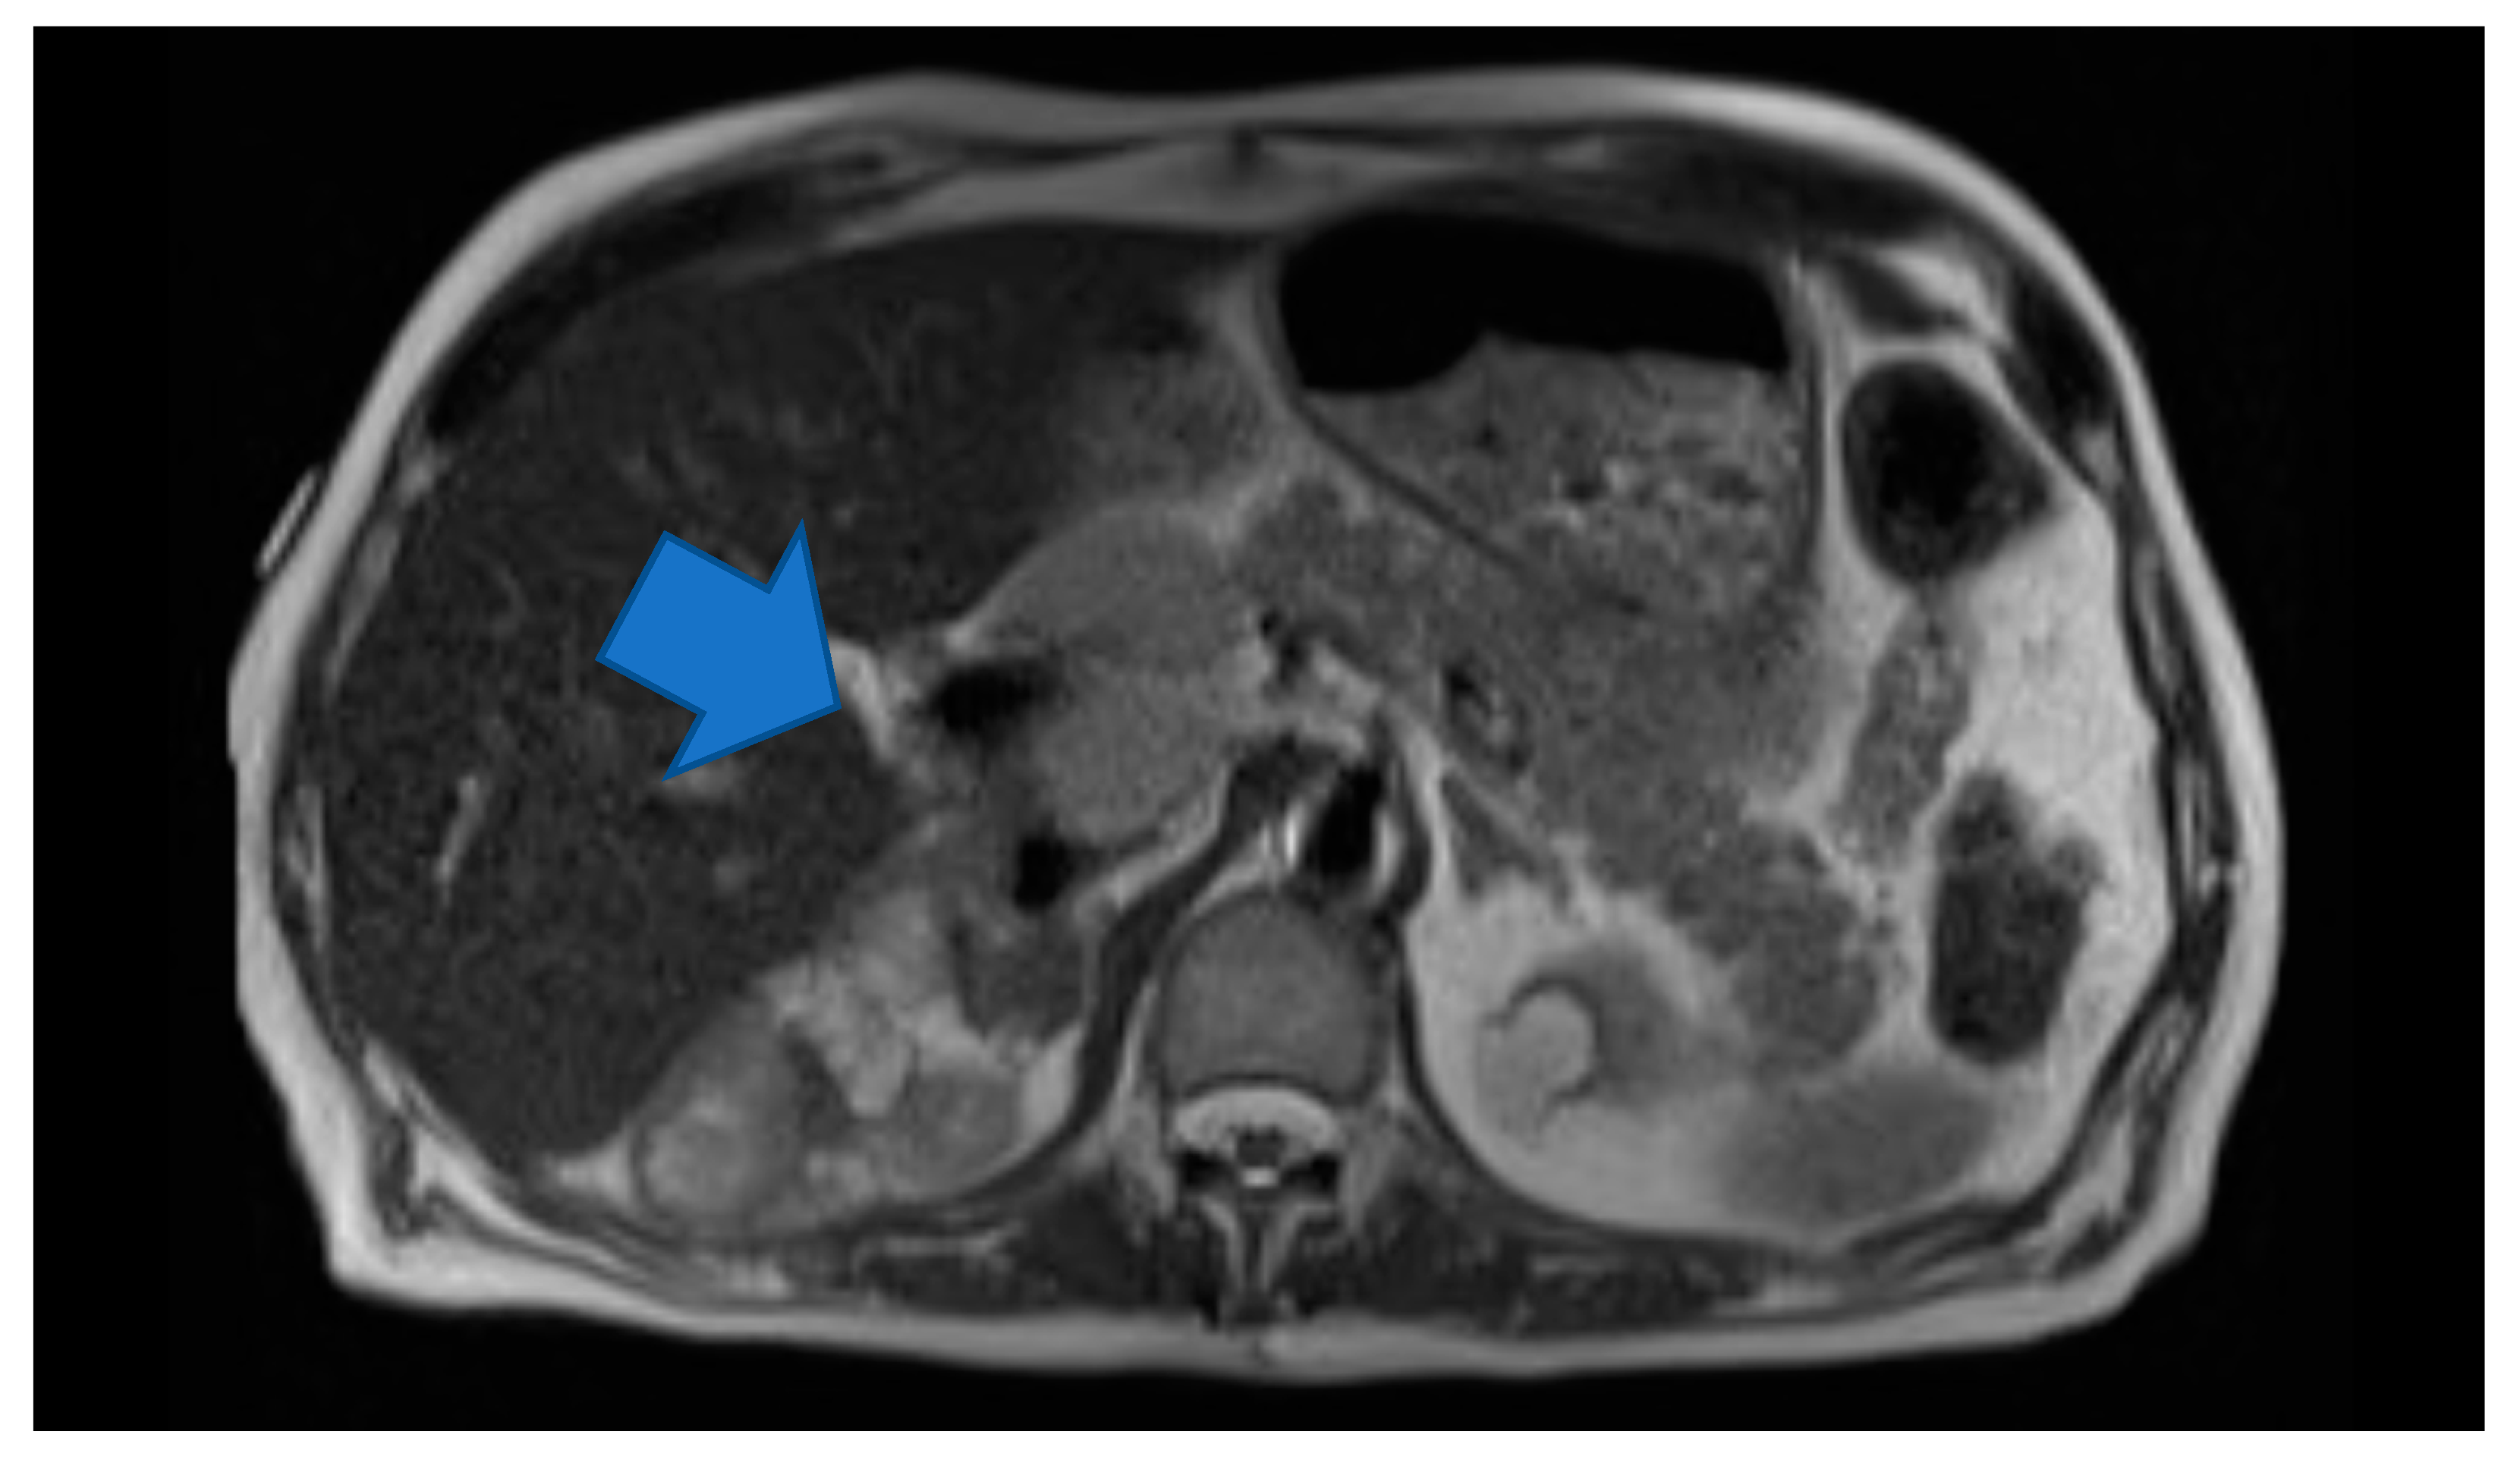

Laboratory testing revealed anemia (hemoglobin 9.2 g/dl) and hyponatremia (sodium 131). His urine metanephrine was 556 mcg/24 h, normetanephrine was 22,624 mcg/24 h and creatinine was 2.56 mg/dl. His INR was 4.26 which was high. On imaging, there was an abdominal mass on the right upper kidney as well as an abdominal hematoma. Computer tomography (CT) of abdomen showed left lower abdominal wall hematoma and prominent multilobulated soft tissue mass within the right retroperitoneum superior to the right kidney in the region of right adrenal gland involving the liver, vena cava and kidney. Magnetic resonance imaging (MRI) of abdomen and pelvis showed postoperative changes after right adrenalectomy with 7.8 cm heterogenous multilocular enhancing mass in the surgical bed abutting the right posterior wall and close to the right kidney and Inferior vena cava (IVC). The mass and the enlarged regional lymph nodes together caused marked compression of the IVC. Heterogeneity and enhancing focus in the posterior right hepatic lobe indicated the invasion of the right adrenal gland. (Figure 1) Positron emission tomography (PET) gallium-68 DOTA-DPhe1, Tyr3-octreotate ((68Ga)Ga-DOTA-TATE) imaging showed liver and mesentery metastases. (Figure 2) He was diagnosed with right metastatic malignant adrenal lesion surrounding IVC along with the syndrome of inappropriate antidiuretic hormone (SIADH).

Figure 1.

Axial HASTE. Large multilocular heterogeneous mass in the right adrenalectomy bed and large regional lymph nodes causing Inferior vena cava (IVC) compression.